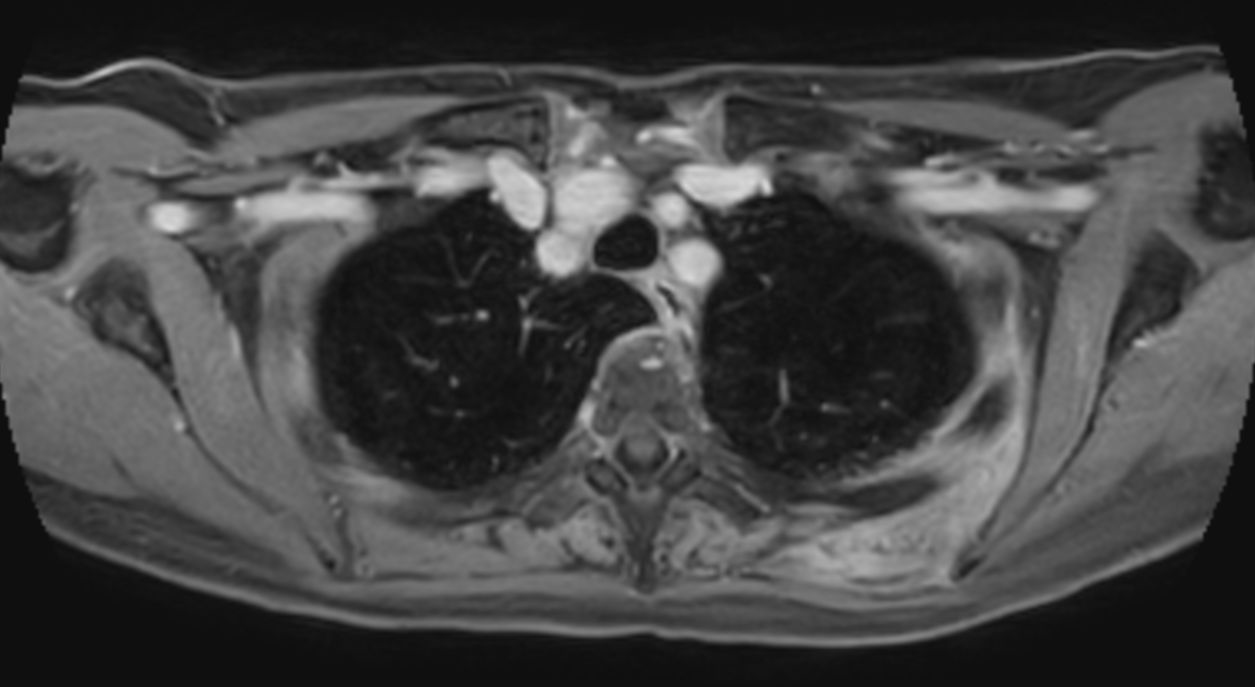

Patient with a thorax soft tissue lesion. ExamCard includes Compressed SENSE to shorten the scan time, MultiVane XD to acquire motion-free diagnostic images, 3D VANE XD helping to reduce motion artifacts during free breathing and 4D FreeBreathing to perform multi-phase contrast-enhanced MRI studies.

T2w TSE - Free Breathing Compressed SENSE